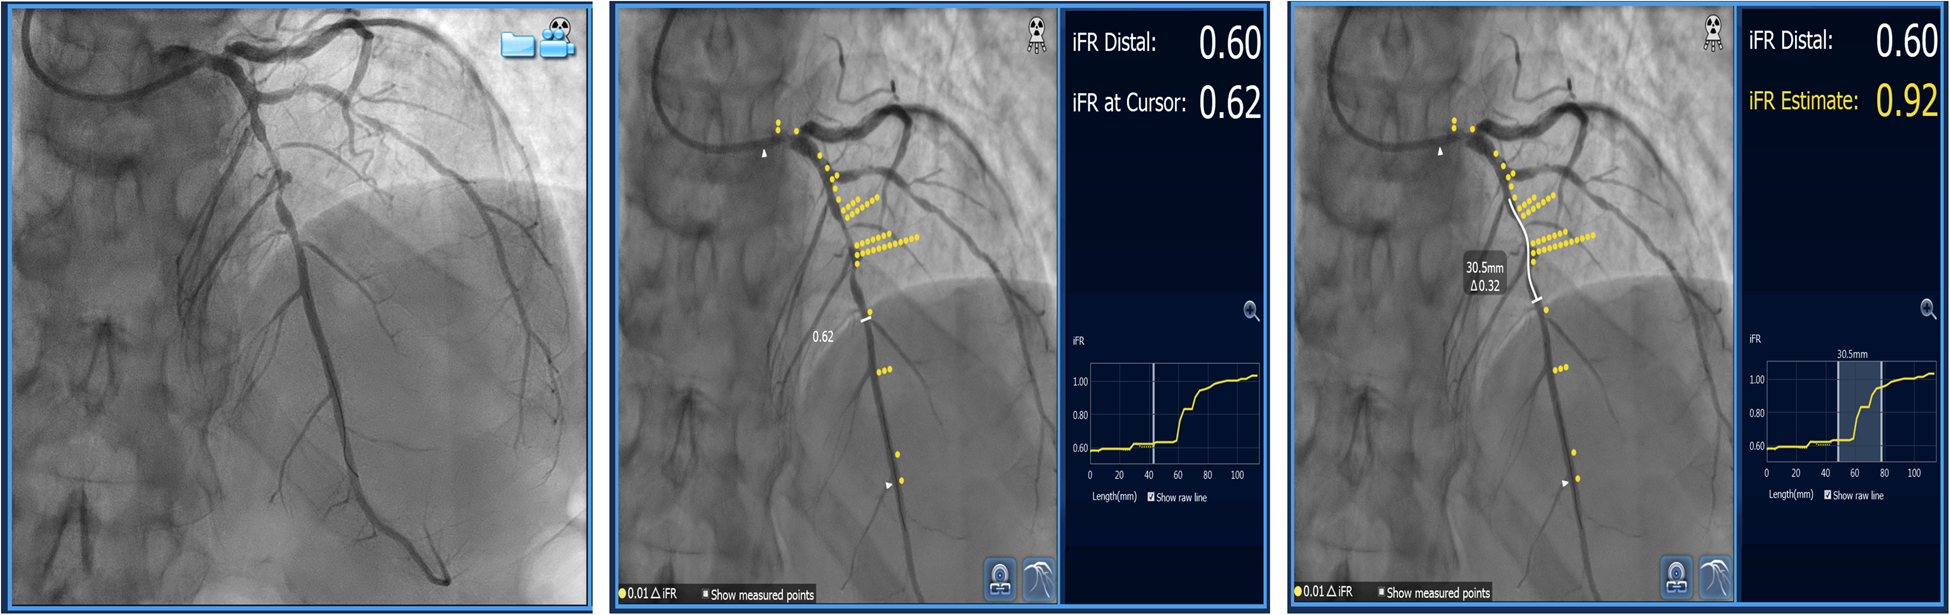

Resting or non-hyperemic indices (NHI) can be used to evaluate serial stenoses. Since they measure pressure differences in different parts of the myocardial contraction cycle, it has been speculated that they might be less affected by the interplay between serial lesions compared to FFR (6). They can be used in a similar manner as FFR by performing a pullback recording. Instantaneous wave-free ratio (iFR) (SyncVision, Philips, The Netherlands) uses co-registration with angiography and can predict each lesion's significance and the effect of PCI on iFR measurement afterward (Figure 4). It was demonstrated in 128 patients (134 diffuse and/or serial lesions) enrolled in the iFR GRADIENT registry that using iFR pullback and a prediction software changed the PCI strategy in almost 1/3 of the patients with an accurate prediction of post-PCI iFR values (15). However, this study was carried out for intermediate-severity lesions and the findings cannot be extrapolated to every serial stenosis regardless of its severity. Also, this method can be applied if the assumed Pw is close to 0 mmHg, and it does not take into account the potential effect of flow diversion if the side branches existed between the lesions. As previously stated, treating one lesion increases coronary flow and may affect iFR and other (NHI) measurements. Knowing this, it would be prudent to retest iFR after treating the lesion with the greatest trans-stenotic gradient and then decide on the treatment of another lesion. Another study by Warisawa et al., compared pullbacks by iFR, FFR, and hyperemic iFR in tandem lesions with the idea of comparing these modalities in determining lesion dominance. The dominant lesion had a greater trans-stenotic gradient. After defining iFR pullback assessment as the reference, they found that FFR-pullback assessment classified the cases differently in 22.7% of the patients (20/88) in the following manner: 23.9% (11/46) proximal predominant cases were re-classified as distal predominance, while 21.4% (9/42) distal predominant cases were re-classified as proximal predominance. Delta iFR and delta FFR did not have a strong correlation in either the proximal or distal lesions (15). The discordance between iFR and FFR was more pronounced in less severe lesions (less diameter stenosis and greater iFR values) while there was no difference regarding lesion length, vessel localization, and size (16). Another study by the same group demonstrated that the pattern of disease, focal vs. diffuse, also significantly influenced the discordance between iFR and FFR pullbacks. The pattern FFR positive/iFR negative was more frequent in focal disease, while FFR negative/iFR positive was seen more often in diffuse disease (17), (Figure 4). These findings warrant caution when interpreting resting indices data in focal disease and serial stenoses, demonstrating similar limitations as previously described in hyperemic FFR.

Figure 4

Serial lesion assessment using iFR and co-registration with “Sync Vision” software (Philips Healthcare, The Netherlands). The images show mid-LAD serial lesions assessed by iFR, and each yellow dot represents a 0.01 value in iFR Reading. The white-butted line in the right image demonstrates the potential effect of stent implantation on iFR value change (ΔiFR).